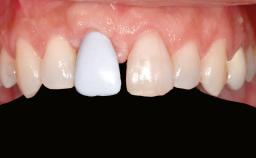

A 46-year-old woman was referred for treatment whose main complaints were mobility of her fixed partial dentures (right maxilla and left mandible) and periodontal bleeding during function. She also reported having taken systemic antibiotics to treat recurrent swelling in the area of the upper left molars. The patient had not seen a dentist for at least 2 years. She did not smoke and had no history of major systemic disease other than two minor orthopedic procedures some years back. The first-visit examination revealed poor plaque control, tooth mobility, periodontal disease, and a residual dentition widely associated with deep periodontal pockets.

Prosthesis Type FDP

Defining Characteristics Up to three missing teeth to be replaced with an implant-borne restoration or restorations